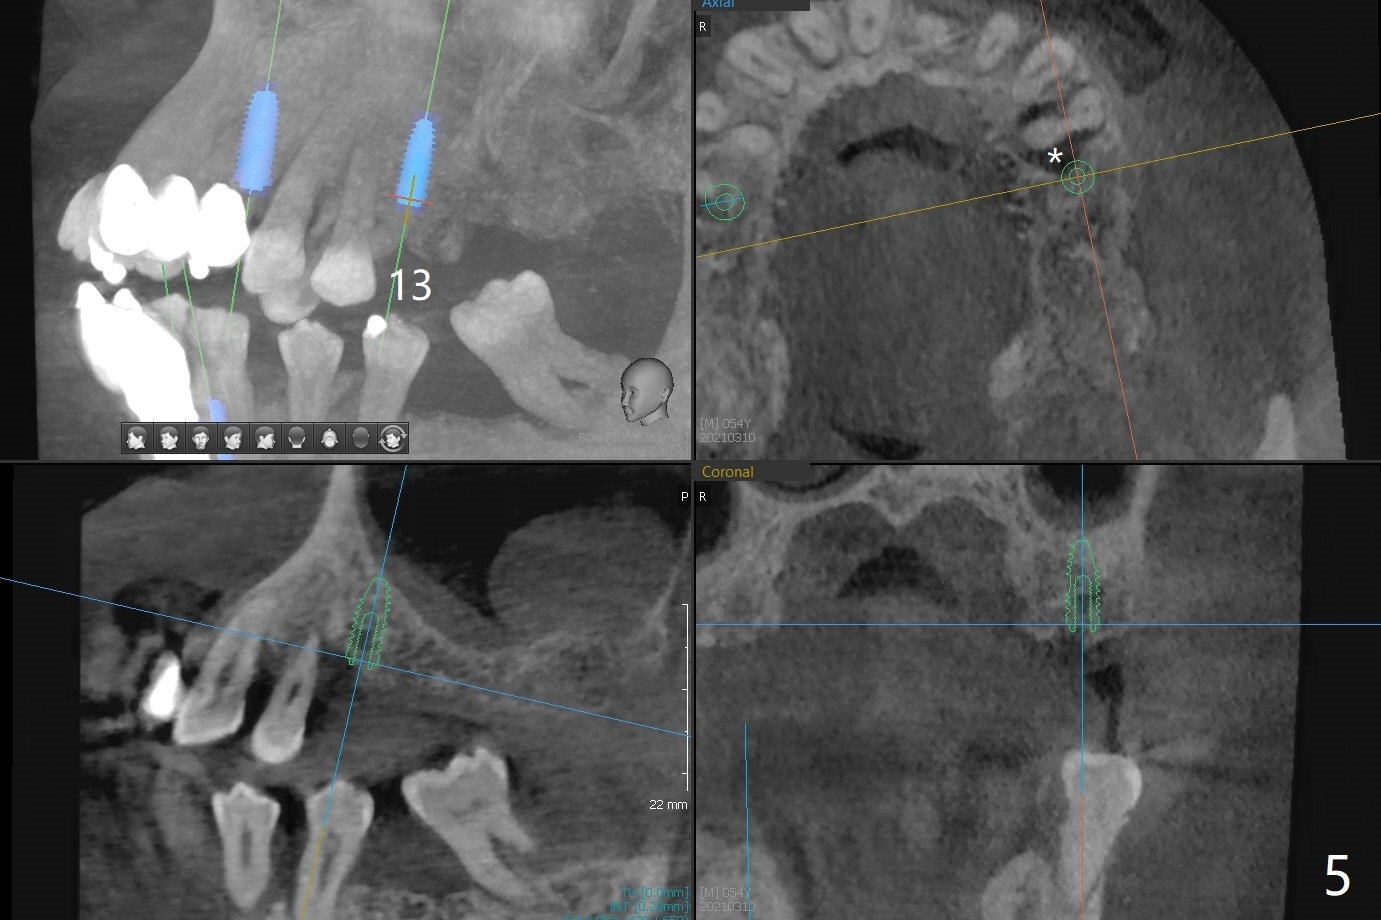

54岁男,28,29植骨后5个月,回来要求3,13,28,29种植(图一)。3号牙需要切开除去残根(图二:*),然后导板种植,准备两个PRF膜。为了保证植牙间距离,尝试在28,29处植入3.5x13毫米植体(图三,四)。在13号牙种植时(图五),考虑12号牙腭侧植骨(图六)。为了减少对12号牙咬合创伤,考虑4个植牙即刻修复。